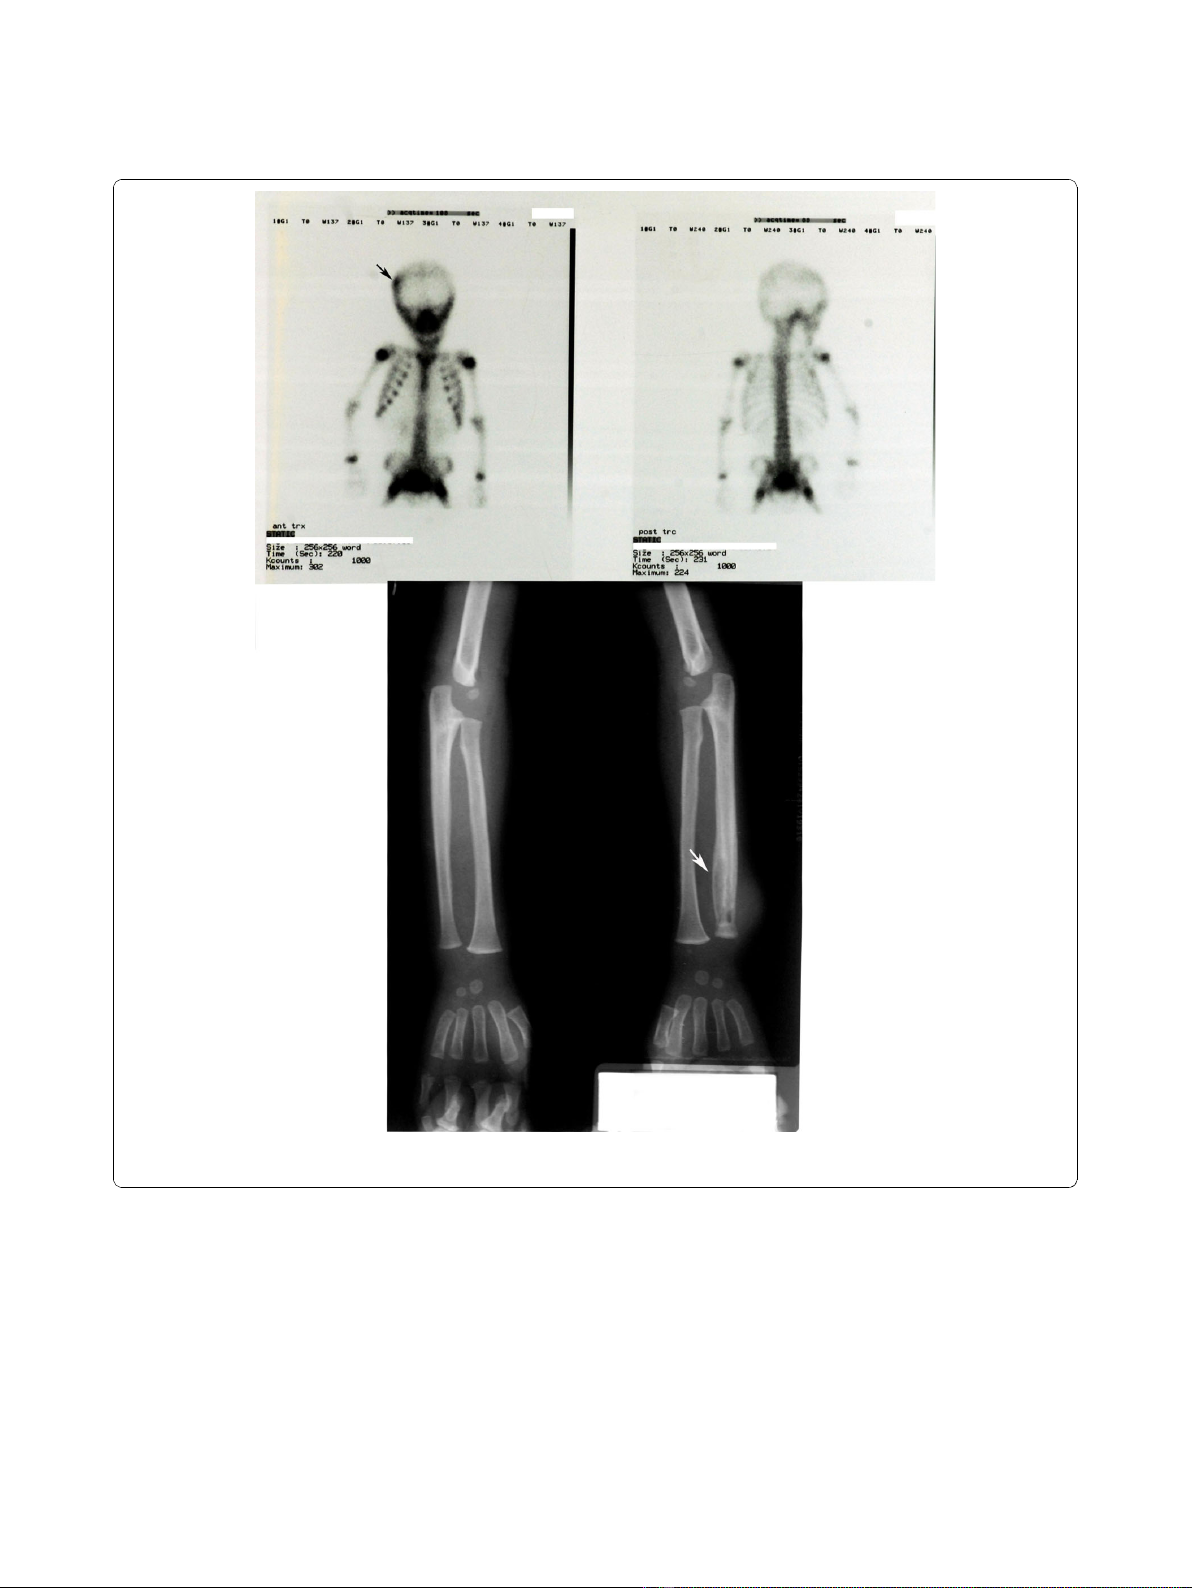

activity was seen on right frontoparietal bone with bone

Tc 99m MDP scintigraphy; X-ray of the distal metaphy-

seal region of the radius revealed osteolytic lesions (Fig-

ure 2). Bone biopsy was planned but parental consent

Figure 2 Bone Tc 99m MDP scintigraphy (a) showing increased activity on right frontoparietal bone: (b) plain radiograph of the

patient showing osteolytic lesions in distal metaphyseal region of the radius.

observed. Recurrent, multifocal, sterile osteomyelitis in

X-rays and bone scintigraphy findings with negative cul-

tures supported the diagnosis of CRMO for our case.